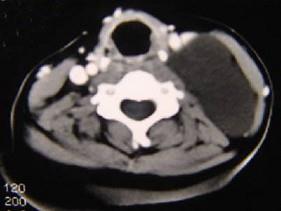

问题 男性,40岁,颈部出现无痛性囊性包块2年余,CT扫描如图所示,最可能诊断为 ( )

选项 A、神经源性肿瘤 B、颈动脉鞘瘤 C、血管瘤 D、淋巴结肿大 E、淋巴管瘤

答案 E